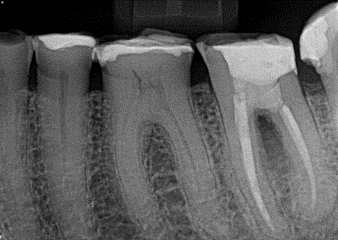

Tooth 4.8 is planned for extraction. Which radiographic findings suggest an increase in the degree of difficulty of the extraction?

Tooth 2.8 is planned for extraction. Which radiographic findings suggest an increase in the degree of difficulty of the extraction?

Tooth 1.8 is planned for surgical extraction. Which radiographic findings suggest an increase in the degree of difficulty of the extraction?

Tooth 2.8 is planned for surgical extraction. Which radiographic findings suggest an increase in the degree of difficulty of the extraction?